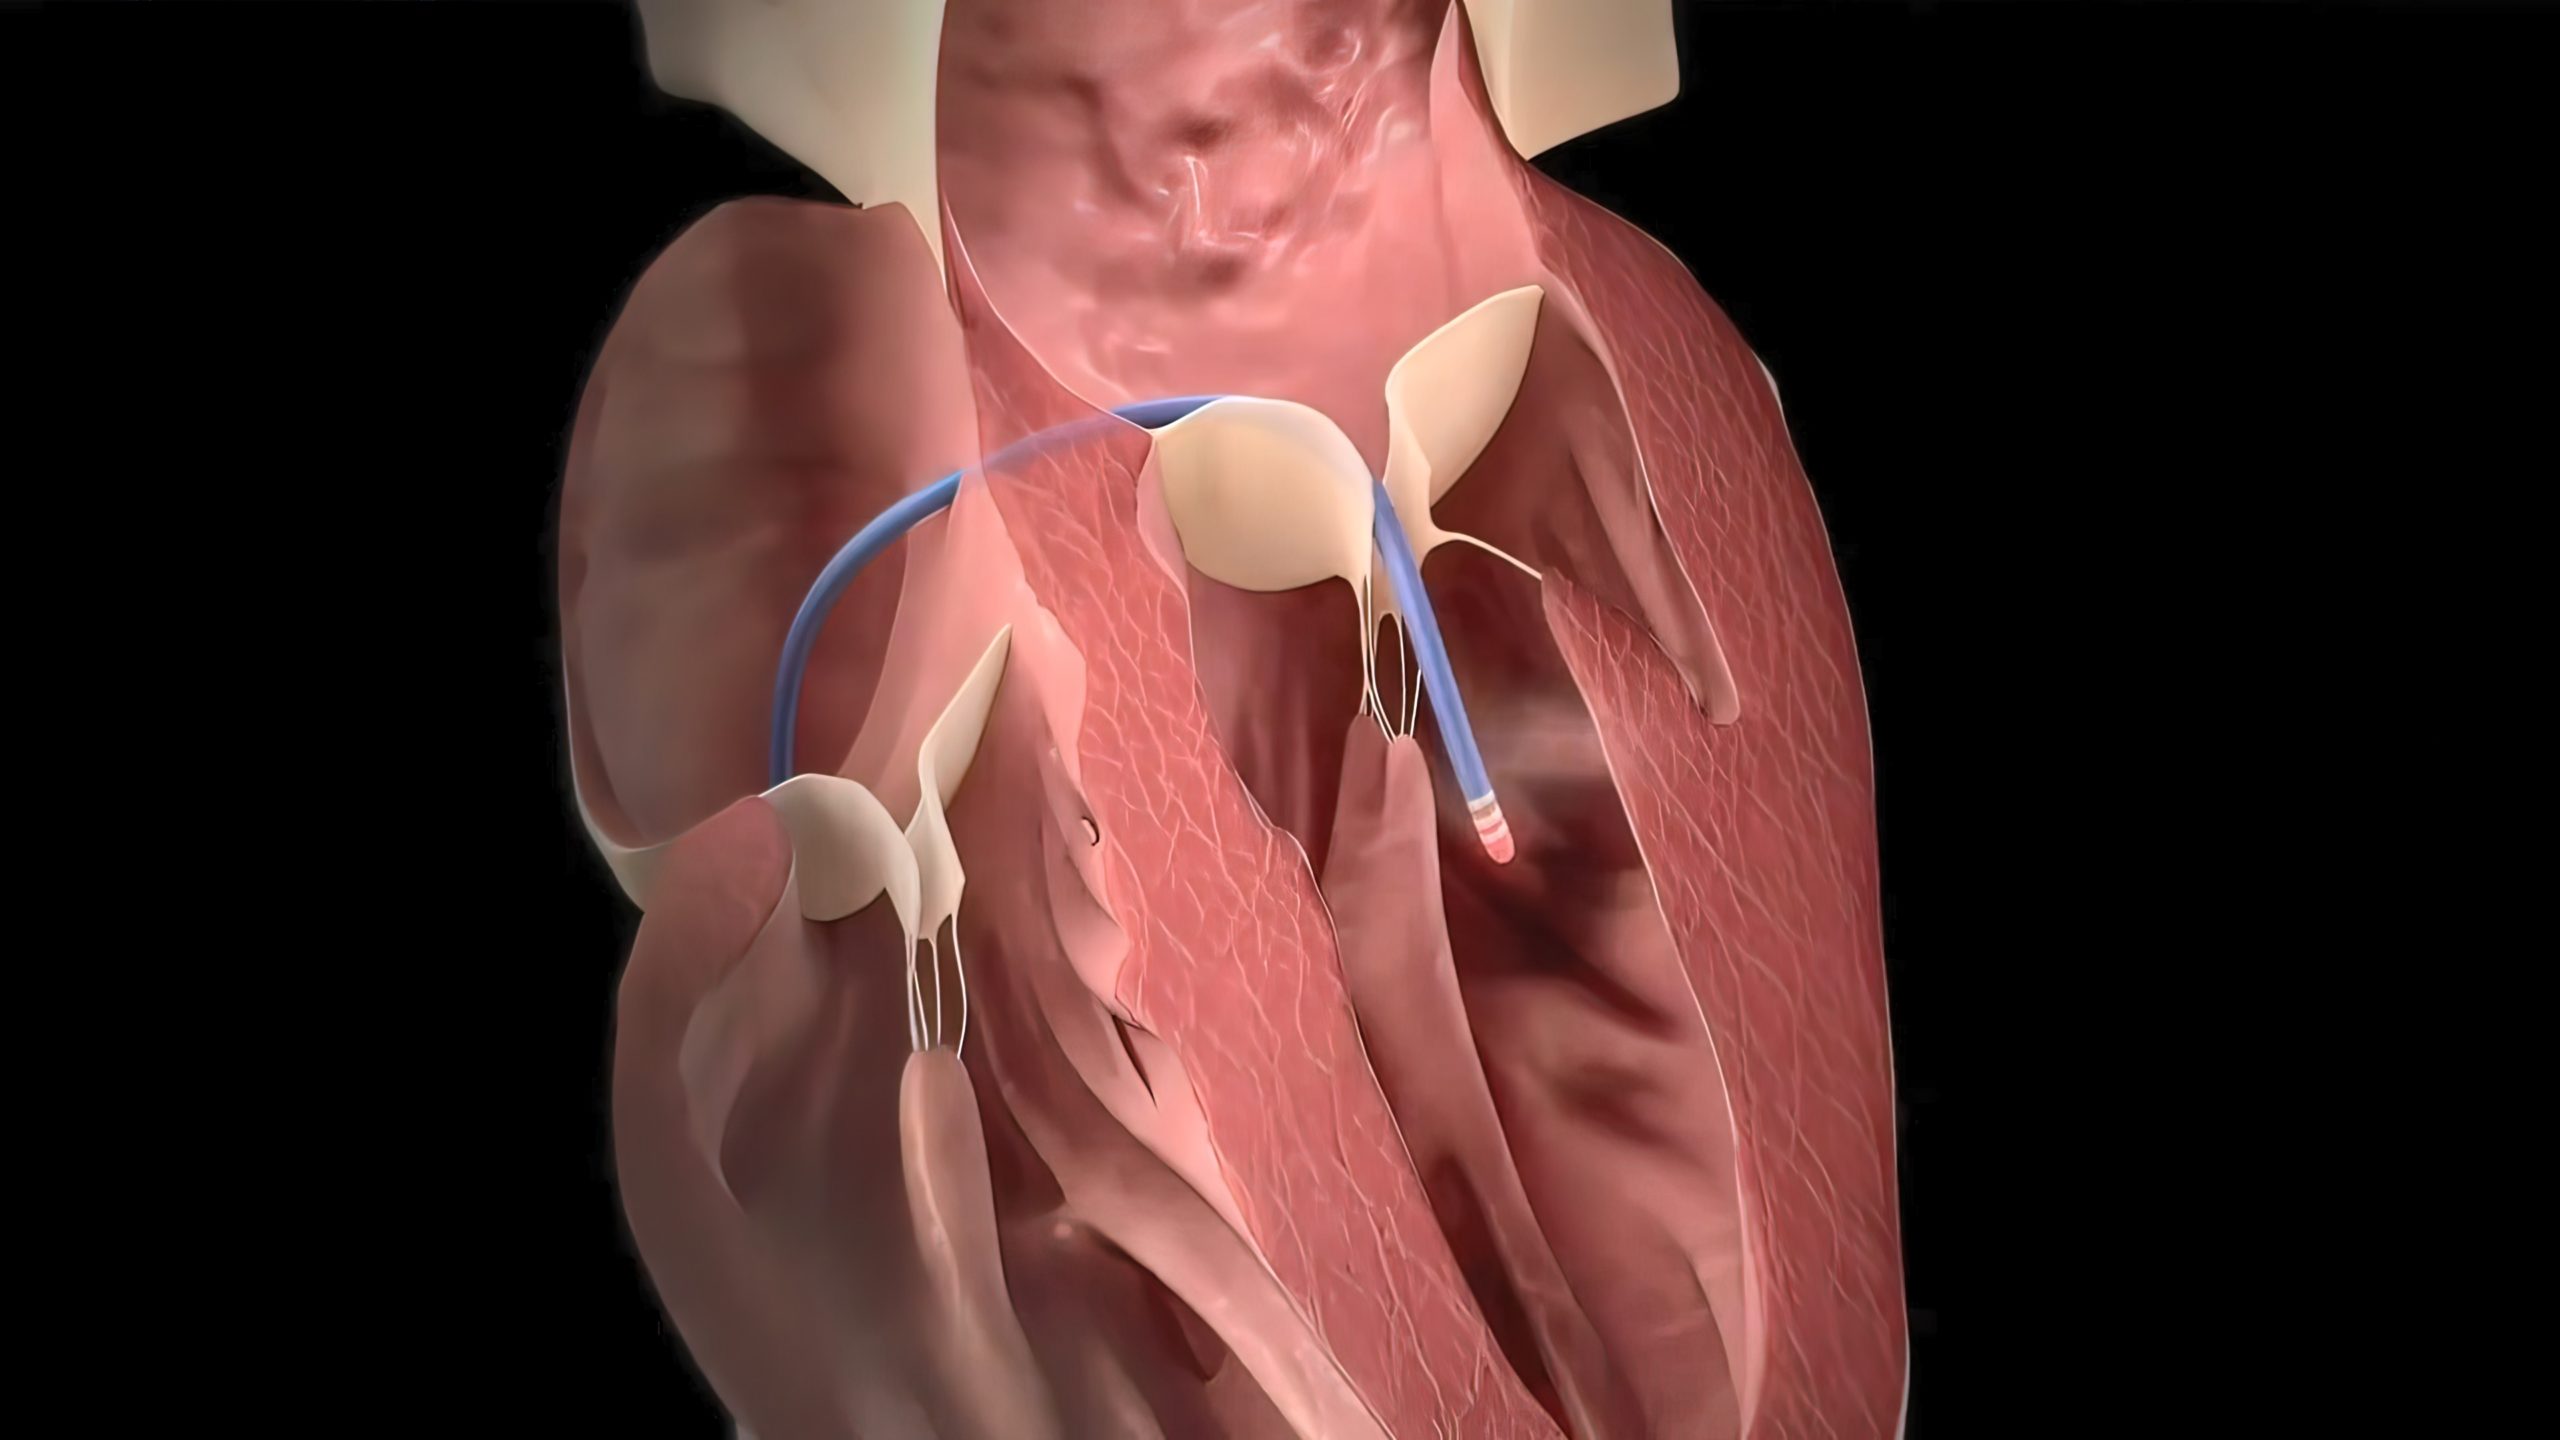

Left atrial appendage preservation during surgical ablation for atrial fibrillation was not associated with an increased ...

Pulmonary vein isolation (PVI) via cryoballoon ablation (CBA) or radiofrequency ablation (RFA) is the standard treatment ...

According to a study in Frontiers in Cardiovascular Medicine, alternative balloon-based approaches are effective ...

A new study shows that intracardiac echocardiography (ICE) and its integration into three dimensional (3D) ...